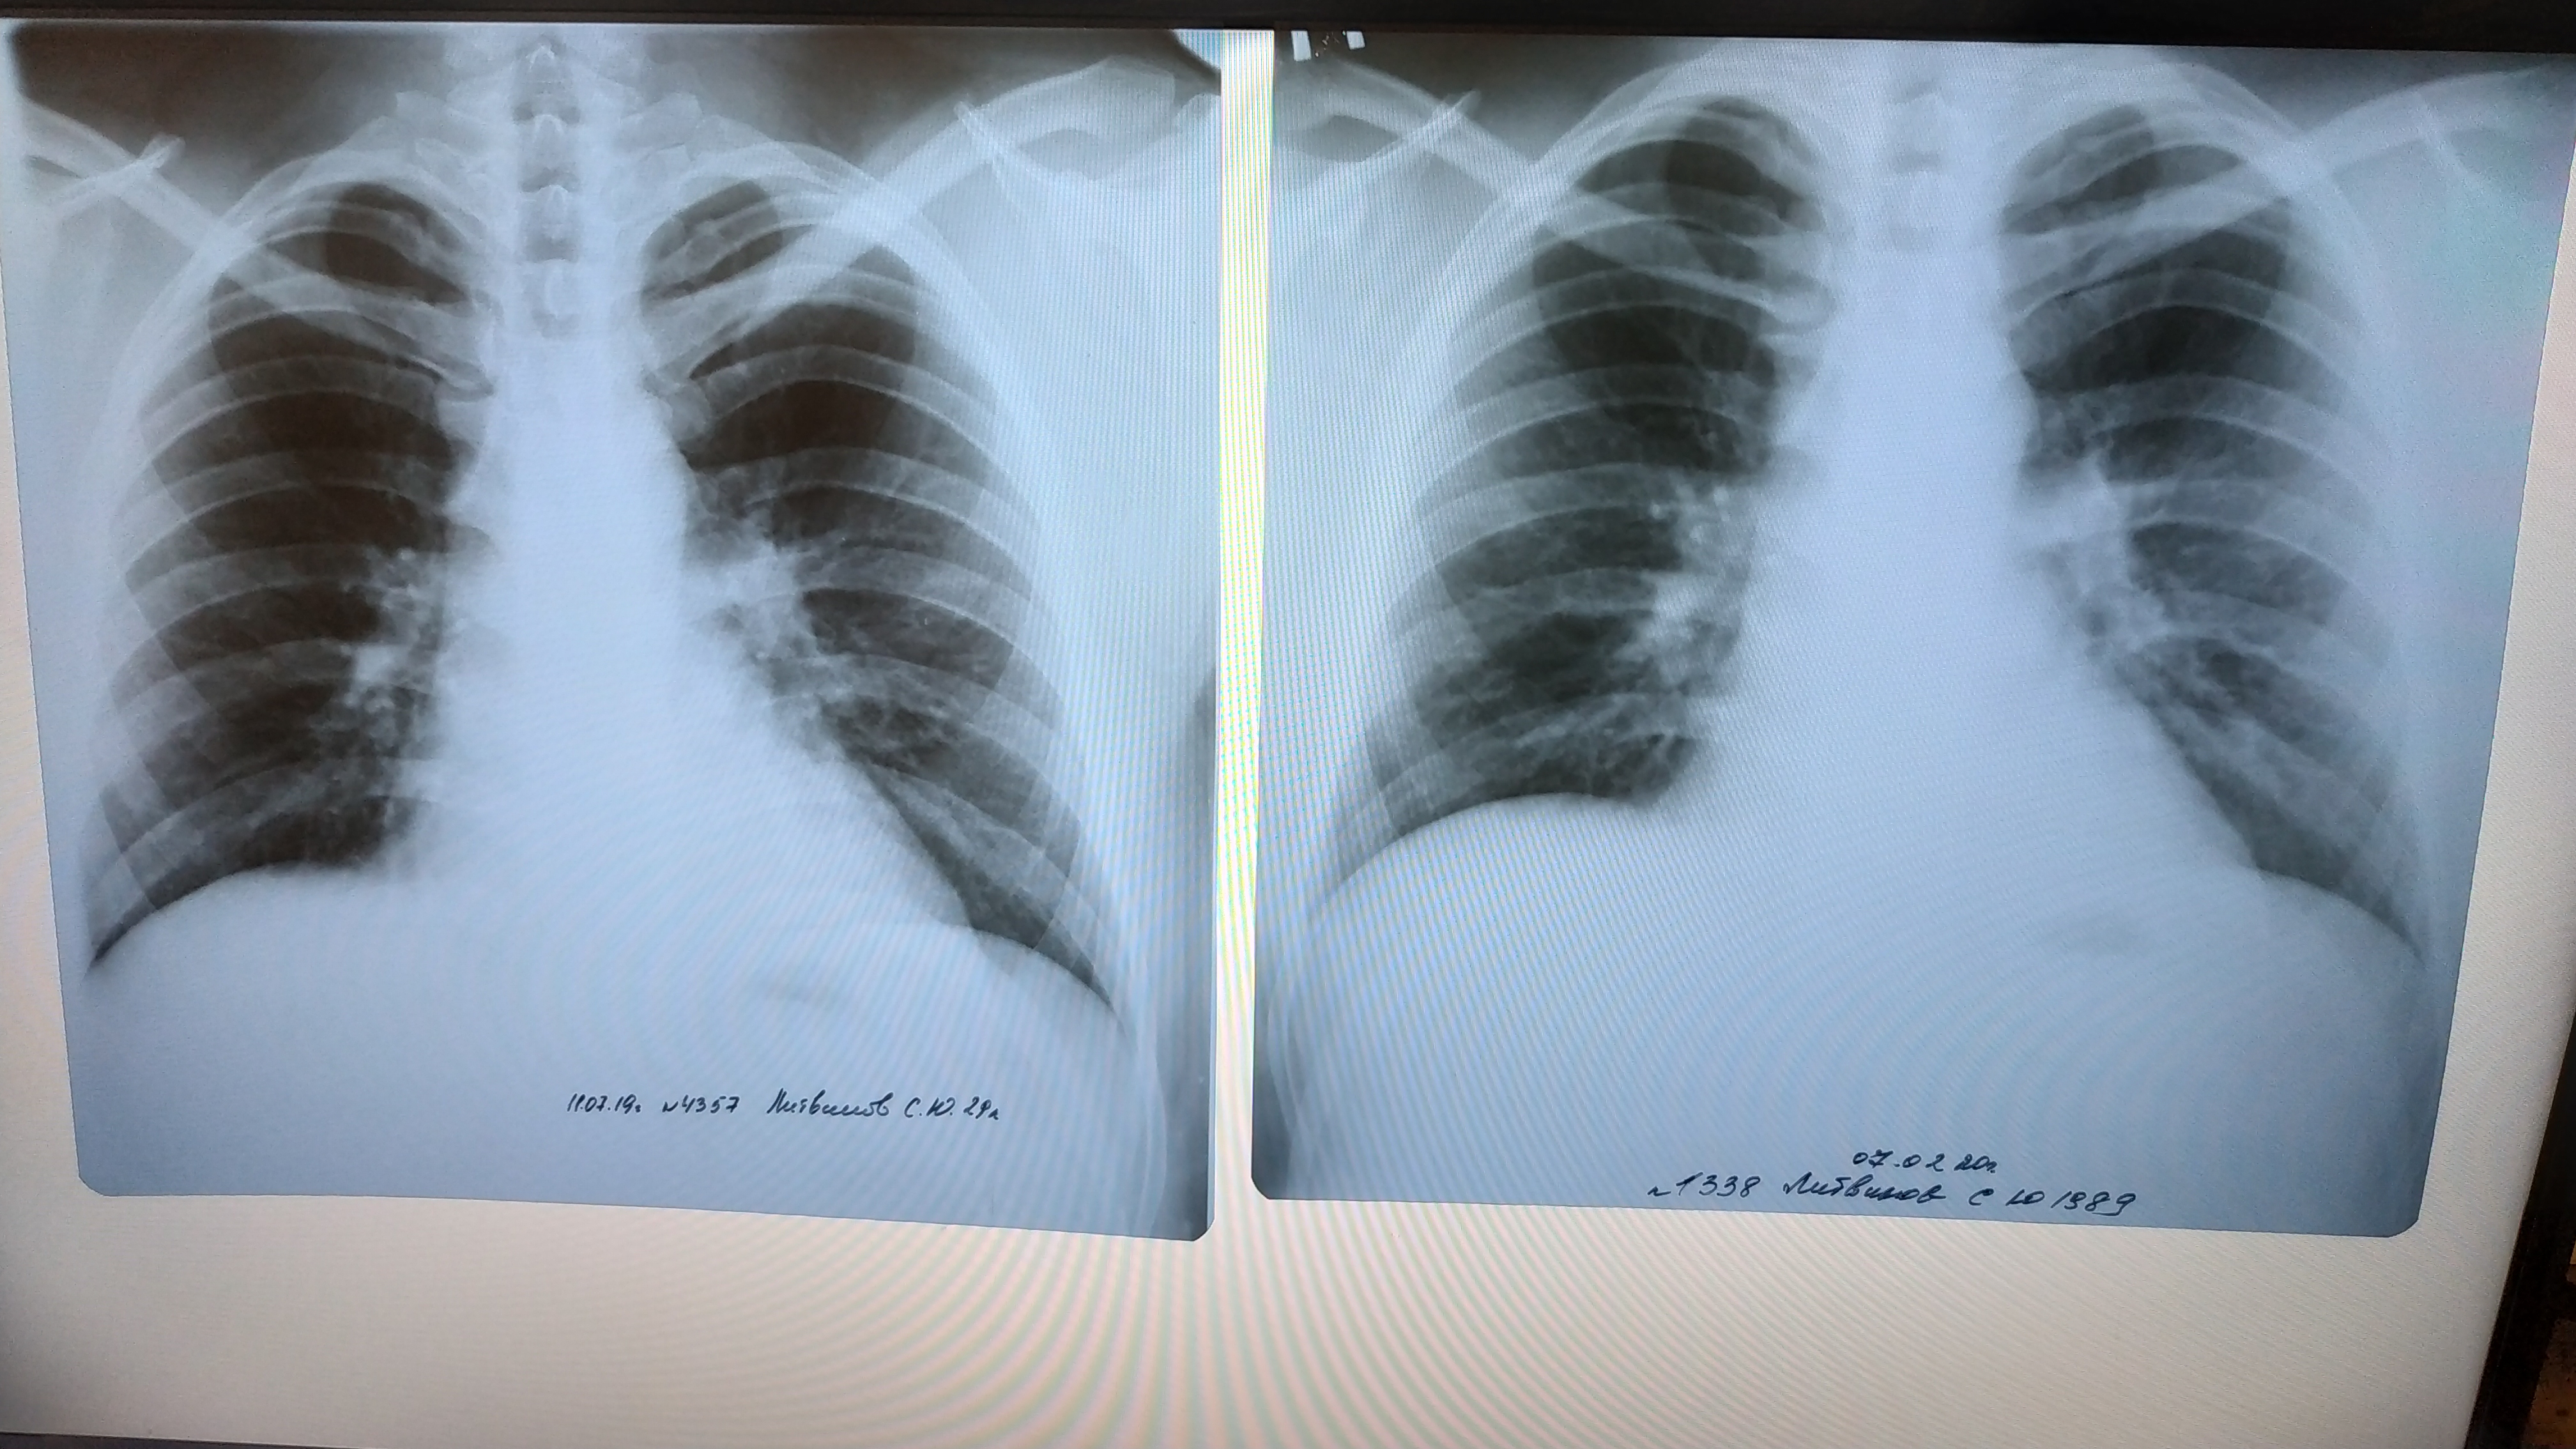

Нормальная рентгенограмма легких: что нужно знать

Раздел: Мудрость в объективе